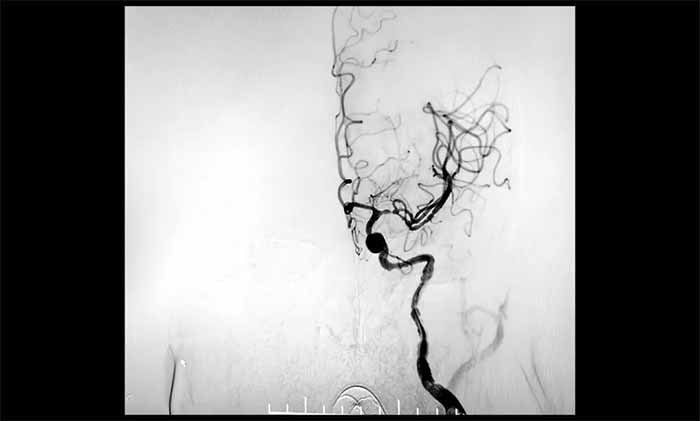

▲ 左颈内动脉顺利开通

二次取栓难度远超首次:患者处于恢复期,血管壁条件较差,存在出血转化风险。在席刚明教授指导下,王贵平博士主刀的介入团队成功取出新鲜血栓,复查造影显示血管再通,血流恢复良好。目前患者正在康复中。